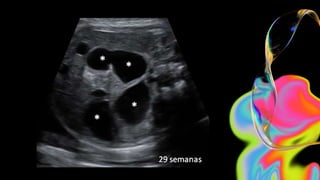

ECOGRAFIA

Hallazgos

Signo del teclado

E N O B S T R U C C I Ó N I N T E S T I N A L

VENTAJAS DESVENTAJAS

No se expone a los pacientes a radiación. Hay largo tiempo de exploración.

Su uso no está limitado por la administración

previa de contraste baritado.

Tiene una menor resolución.

Son similares a los hallazgos en TC